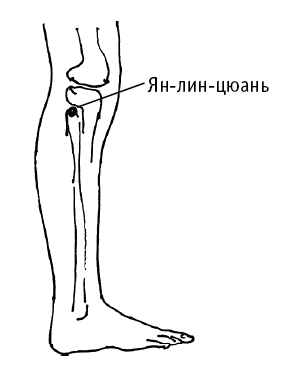

Ян-лин-цюань («родник у холма на наружной стороне колена») расположена под коленом, на внешней стороне голени.

Точка используется для лечения следующих расстройств желудочно-кишечного тракта: понос, тошнота, рвота, вздутие живота, снижение аппетита, боль в эпигастральной области.

Дополнительный эффект от воздействия на точку: уменьшение головных болей, болей в подреберье; лечение колена, поясницы, болей в тазобедренном суставе, болей и судорог в голени и стопе.

Ян-лин-цюань («родник у холма на наружной стороне колена») расположена под коленом, на внешней стороне голени.

Точка используется для лечения следующих расстройств желудочно-кишечного тракта: понос, тошнота, рвота, вздутие живота, снижение аппетита, боль в эпигастральной области.

Дополнительный эффект от воздействия на точку: уменьшение головных болей, болей в подреберье; лечение колена, поясницы, болей в тазобедренном суставе, болей и судорог в голени и стопе.